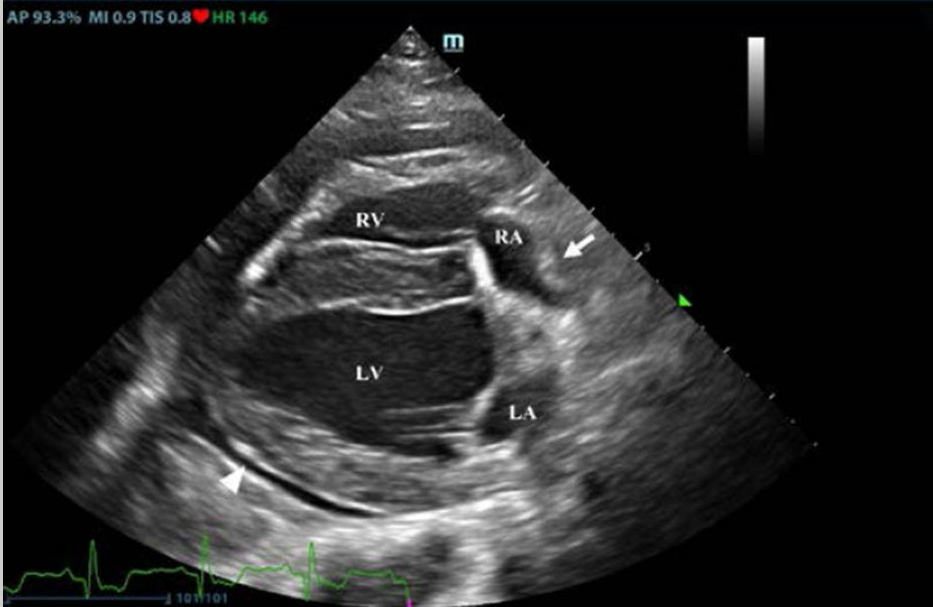

Echocardiography

Echocardiography is the GOLD STANDARD for diagnosing pericardial effusion. Point-of-care ultrasound (POCUS) using the TFAST protocol and the diaphragmatico-hepatic (DH) view is highly sensitive and can be performed rapidly in emergency settings.

Key Echocardiographic Findings

- Anechoic/hypoechoic space: Echo-free space between pericardium and epicardium

- Cardiac swinging: Heart moves back and forth within fluid

- Right atrial collapse: During diastole; indicates tamponade physiology

- Right ventricular collapse: In early diastole; more severe tamponade

- Cardiac masses: Right atrial (hemangiosarcoma) or heart base (chemodectoma)

- Dilated hepatic veins and caudal vena cava: Indicates elevated right-sided pressures

Figure 5 - Right parasternal echocardiogram showing anechoic pericardial effusion surrounding the heart with visible right atrial collapse during diastole. (A) Echocardiography in parasternal long axis. Arrow shows the posterior displacement of the apex and the lack of the typical round left ventricular apex. Cardiovascular magnetic resonance showing the clockwise rotation. Compared with the prone position (B), leftward posterior rotation of the heart is seen in when patient is in supine position (C).

Reference:Pérez-Casares A, Cesar S, Brunet-Garcia L, Sanchez-de-Toledo J. Echocardiographic Evaluation of Pericardial Effusion and Cardiac Tamponade. Front Pediatr. 2017 Apr 24;5:79. doi: 10.3389/fped.2017.00079. PMID: 28484689; PMCID: PMC5401877.

Board Tip: Echocardiography has a sensitivity of 82% and specificity of 100% for detecting cardiac masses in dogs with pericardial effusion. However, masses may not be visible in cases of mesothelioma (diffuse disease) or early hemangiosarcoma. The pericardial effusion itself provides excellent acoustic contrast to help identify masses - so perform echo BEFORE pericardiocentesis if the patient is stable enough.